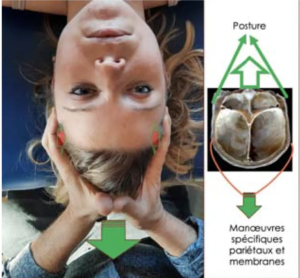

- Integración de técnicas osteopáticas en RPG: Mejorar la movilidad articular y el equilibrio postural en la postura de estiramiento.

- Estudio de movimientos intrínsecos del cráneo: Diferenciar entre movimientos causados por estructuras inferiores y deformaciones propias del cráneo.

El curso se desviará de algunas ideas osteopáticas tradicionales, centrándose en los principios RPG y respetando los descubrimientos actuales en ciencias médicas. Además, se abordarán las estructuras intracraneales y su influencia en la postura, destacando la importancia de la duramadre y las membranas de tensión recíproca en el equilibrio de tensiones y la salud del sistema nervioso central.